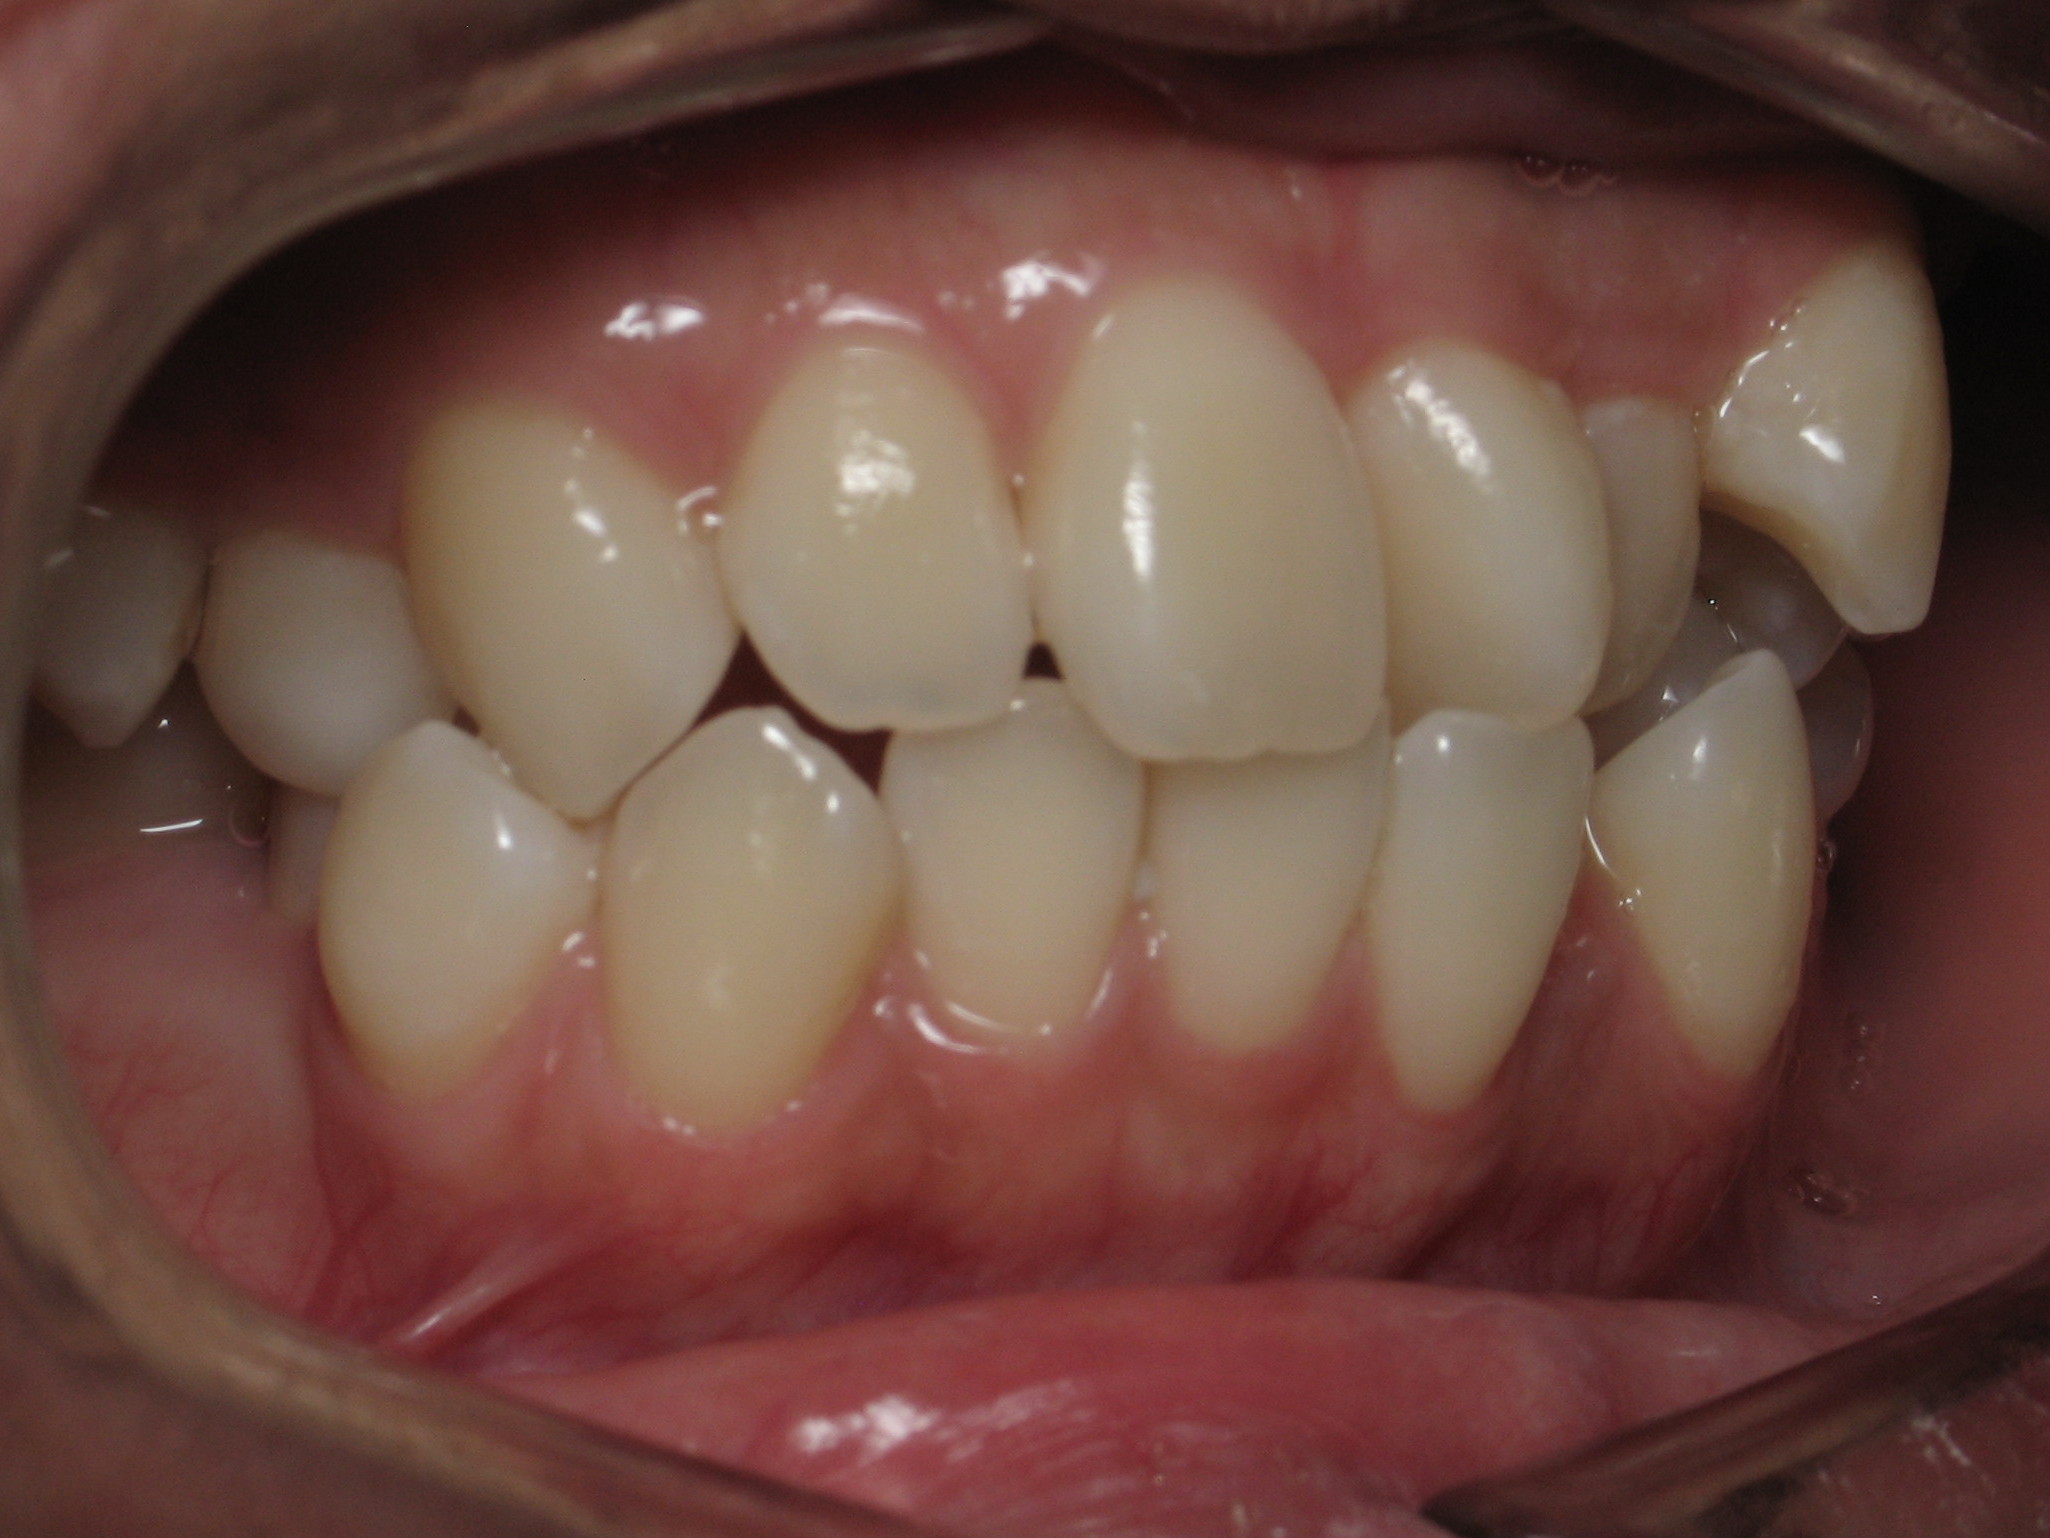

Orthodontic Treatment X-ray - Before

After Series of Teeth Extractions, Upper Left Canine Unerupted.

Ready to Start Ortho Treatment